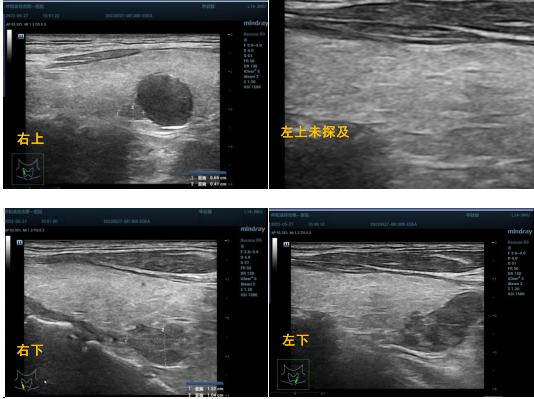

图3(组合).术前甲状旁腺超声定位

严重的高PTH血症, ALP持续性增高:血PTH及ALP水平与疾病严重程度有关。一般认为甲状旁腺素( PTH ) >800pg/mL时须行手术治疗。手术入选标准:SHPT合并严重的临床症状,如骨关节痛、肌无力、皮肤瘙痒及尿毒症小动脉病等,可以无症状持续性非医源性高钙血症或钙磷乘积大于70,全段PTH大于800pg/mL,活性VD药物治疗抵抗。彩超:甲状旁腺增大,任何一个直径大于1cm,或体积大于0.5cm3,有丰富血流肝功能及凝血指标正常。